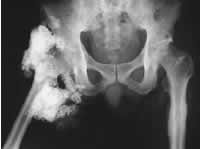

假性甲状旁腺功能低下伴髋关节周围大块钙化

1例55岁的老年男性,有24年2型假性甲状旁腺功能低下病史,其右臀部有一大肿物,行走困难。就诊时发现其血清钙水平低(5.2 mg/dk),磷酸盐高9.1 mg/dk;尿磷酸的排泄不增加,对于甲状旁腺激素有反应,尿排泄环磷腺苷正常。患者曾接受维生素D、铝凝胶和碳酸钙治疗。后来血清钙和磷水平被很好地控制,但发生了慢性肾衰和步态不稳。体格检查在病人右臀部皮下触及一大的硬肿块,病人右髋关节所有方向的运动范围严重受限。X线平片显示,在右髋关节周围钙化扩散。病人右臀部的创伤史可能是这一不对称性钙化发生的原因。, 百拇医药